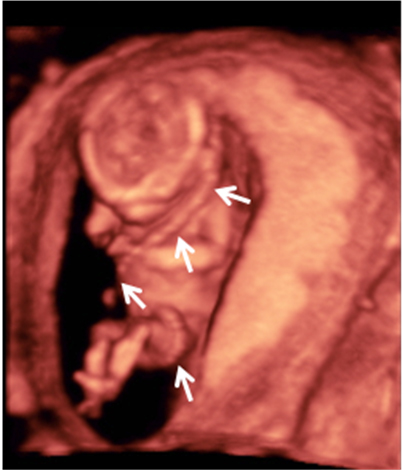

Con la ecografía de la semana 12 de embarazo se pueden detectar algunos signos (marcadores) característicos de los fetos con alguna anomalía cromosómica. Uno de ellos es el ángulo que forman el maxilar superior y el hueso frontal.

Se mide el ángulo que forman el maxilar superior y el hueso frontal. Los valores están tabulados por semana de embarazo. Cuándo este ángulo es mayor de lo normal, existe mayor riesgo de que ese feto tenga síndrome de Down. Es anormal en aproximadamente el 45% de los fetos con síndrome de Down.